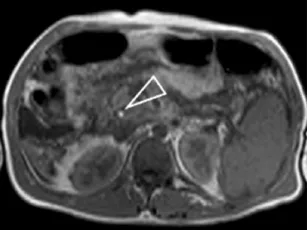

Figure 1. Patient exploré par bili-IRM pour une suspicion de migration lithiasique.

A. Cette coupe de bili-IRM 2D montre de multiples lithiases vésiculaires, ainsi qu’un calcul du bas cholédoque (tête de flèche).

B. Sur cette projection cholangiographique « MIP » issue d’une acquisition 3D en coupes fines, le calcul cholédocien est trop

petit au sein de cette VBP dilatée, et il n’est pas correctement visualisé. En cas de bili-IRM 3D, l’analyse de chacune des coupes

fines du volume est impérative. Ainsi, contrairement à la projection « MIP », la coupe fine passant par le cholédoque permet

de bien montrer le calcul (C)